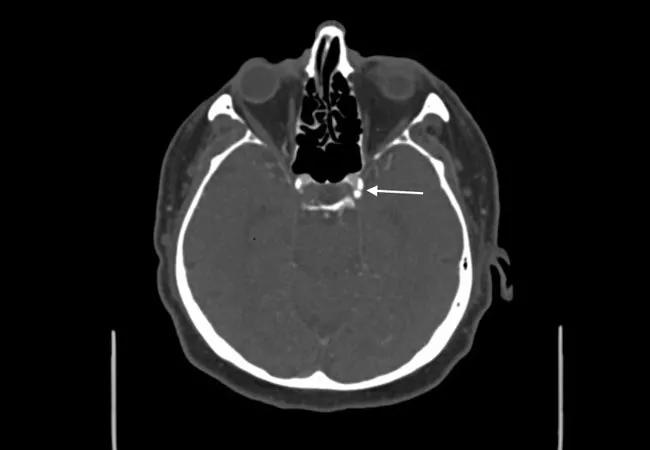

Calcification (arrow) in the intracranial carotid artery of a patient with acute ischemic stroke

Image at top shows calcification (arrow) in the intracranial carotid artery of a patient with acute ischemic stroke.